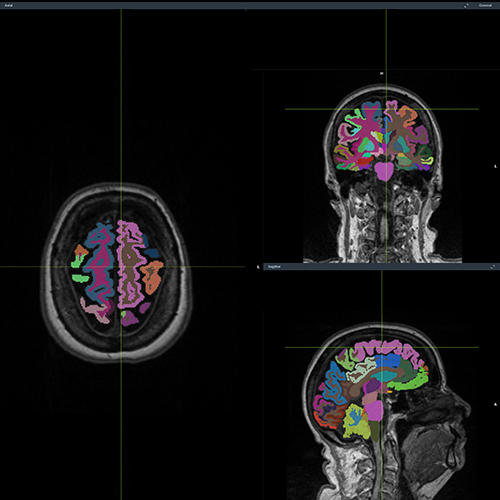

VUNO Med®-DeepBrain™

Brain volumetry using MRI

can aid

diagnosis and monitoring

of a

variety of neurodegenerative

diseases. 7